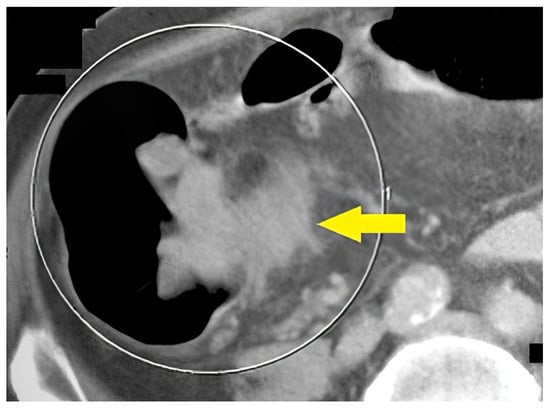

The last example of our experience is a 67-year-old male (Figure 7) who underwent incomplete fibrocolonoscopy, which was not completed because of stenosis of the intestinal lumen due to functional transitional spasm. Afterward, CT colonography was performed, which showed carcinoma of the stomach with metastasis in the liver.

Figure 7.

A 67-year-old patient. CT scan, axial view. Incomplete FCS with suspicion of functional spasm. Normal intraluminal view on FCS. After CT colonography, a stomach carcinoma with liver metastases was found (yellow arrow).